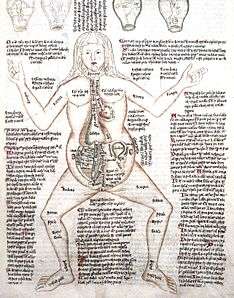

Human anatomy

Humans have the overall body plan of a mammal. Humans have a head, neck, trunk (which includes the thorax and abdomen), two arms and hands, and two legs and feet.

Generally, students of certain biological sciences, paramedics, prosthetists and orthotists, physiotherapists, occupational therapists, nurses, and medical students learn gross anatomy and microscopic anatomy from anatomical models, skeletons, textbooks, diagrams, photographs, lectures and tutorials, and in addition, medical students generally also learn gross anatomy through practical experience of dissection and inspection of cadavers. The study of microscopic anatomy (or histology) can be aided by practical experience examining histological preparations (or slides) under a microscope. [39]

Human anatomy, physiology and biochemistry are complementary basic medical sciences, which are generally taught to medical students in their first year at medical school. Human anatomy can be taught regionally or systemically; that is, respectively, studying anatomy by bodily regions such as the head and chest, or studying by specific systems, such as the nervous or respiratory systems.[2] The major anatomy textbook, Gray's Anatomy, has been reorganized from a systems format to a regional format, in line with modern teaching methods.[40][41] A thorough working knowledge of anatomy is required by physicians, especially surgeons and doctors working in some diagnostic specialties, such as histopathology and radiology. [42]